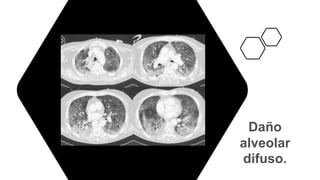

Imagen.

• Rx de tórax influenza que tengan:

• Exploración pulmonar anormal

• Sospecha de neumonía

• Tomografía de tórax:

• Desaturación

• Radiografía de tórax con datos sugestivos de neumonía

• Algunos patrones tomográficos frecuentes en influenza son:

• Vidrio despulido

• Engrosamiento de pared bronquial

• Localización difusa

Daño

alveolar

Imagen. • Rx detórax influenza que tengan: • Exploración pulmonar anormal • Sospecha de neumonía • Tomografía de tórax: • Desaturación • Radiografía de tórax con datos sugestivos de neumonía • Algunos patrones tomográficos frecuentes en influenza son: • Vidrio despulido • Engrosamiento de pared bronquial • Localización difusa Prevención, diagnóstico y tratamiento de la Influenza estacional. Guía de Práctica Clínica: Guía de Referencia Rápida: México, CENETEC; 2020